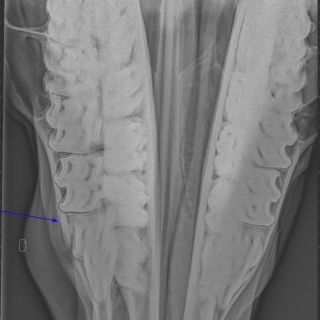

Radiologie (digital)

• Lahmheitsdiagnostik

Orthopädie